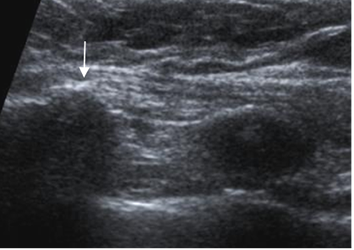

Fig 33 A. Costocondritis.

Ecografía. Lado izquierdo normal. En el lado derecho hay prominencia de la articulación condroesternal, con formación de osteofitos (Flecha), por cambios degenerativos.